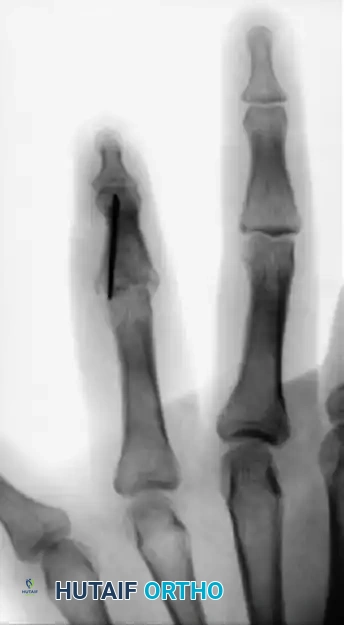

FIGURE 67-72: Malunited fracture of the fifth metacarpal neck treated by open reduction and fixation with one Kirschner wire inserted obliquely. This is rarely necessary because the normal motion of the fifth carpometacarpal joint permits tolerance of up to 40 degrees of angulation at the fracture site.